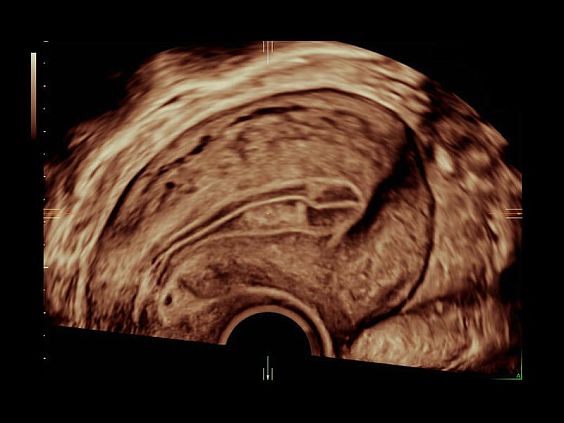

Клинические изображения

Объемное сканирование Voluson — 3D/4D вашей мечты

Объемное УЗИ на Voluson E10 — это не просто потрясающе красивая картинка, это ценный инструмент получения дополнительной информации при обследовании женщин.

Voluson E10 поддерживает инновационные технологии формирования изображений — HDlive Silhouette и HDlive Flow, которые позволяют увидеть мельчайшие детали. Алгоритм SonoRenderlive упрощает рабочий процесс и дает возможность реконструировать изображение поверхностей, определяя область перехода между тканью и жидкостью.